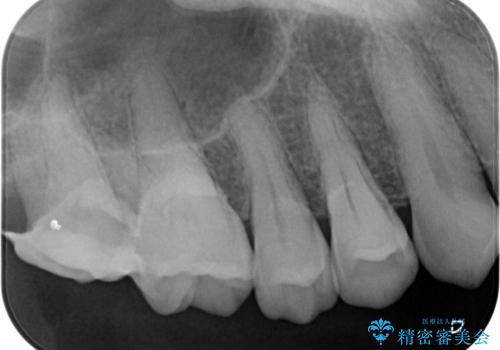

レントゲン写真などで診査を行ったところ、神経組織が壊死し、根尖部周辺の骨に炎症が認められました。

補綴後6ヶ月経過しレントゲンを撮影したところ、根尖周辺の病変が消失していることが確認できました。